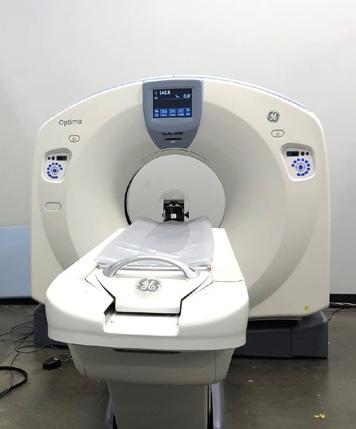

Tri-Imaging Solutions understands the critical role a GE Optima 660 CT scanner plays in delivering accurate diagnostic imaging and patient care. With its comprehensive service packages, expert training, quality parts, and tailored savings plans, Tri-Imaging Solutions ensures the system operates efficiently and cost-effectively. Tri-Imaging Solutions offers:

• Expertise and Reliability: With years of experience in the medical imaging field, Tri-Imaging Solutions is a trusted partner. Its certified engineers are specially trained on GE systems.

• Comprehensive Service Options: Service plans are designed to fit the unique needs of each facility. From full-service contracts to preventative maintenance, Tri-Imaging Solutions offers flexibility and peace of mind.

• Industry-Leading Training: Tri-Imaging offers hands-on, in-depth training programs tailored specifically for the GE Optima 660. The training ensures that your team

knows how to operate the system to its full potential, improving diagnostic accuracy while reducing the likelihood of technical errors. Tri-Imaging Solutions empowers your staff to become experts in their field.

• Genuine Parts and Components: Tri-Imaging Solutions stocks a vast inventory of OEM and high-quality third-party parts for the GE Optima 660. A quick turnaround on parts delivery helps minimize downtime and ensures the scanner continues to function at peak efficiency.

• Cost-Effective Savings Plans: Tri-Imaging Solutions’ savings plans are designed to keep your budget in check without sacrificing service quality. From discounted parts to flexible payment options on service contracts, Tri-Imaging Solutions makes it easy to manage costs over the life of your equipment. With Tri-Imaging Solutions, facilities get premium service at a competitive price, ensuring facilities get a long life out of a Optima 660.